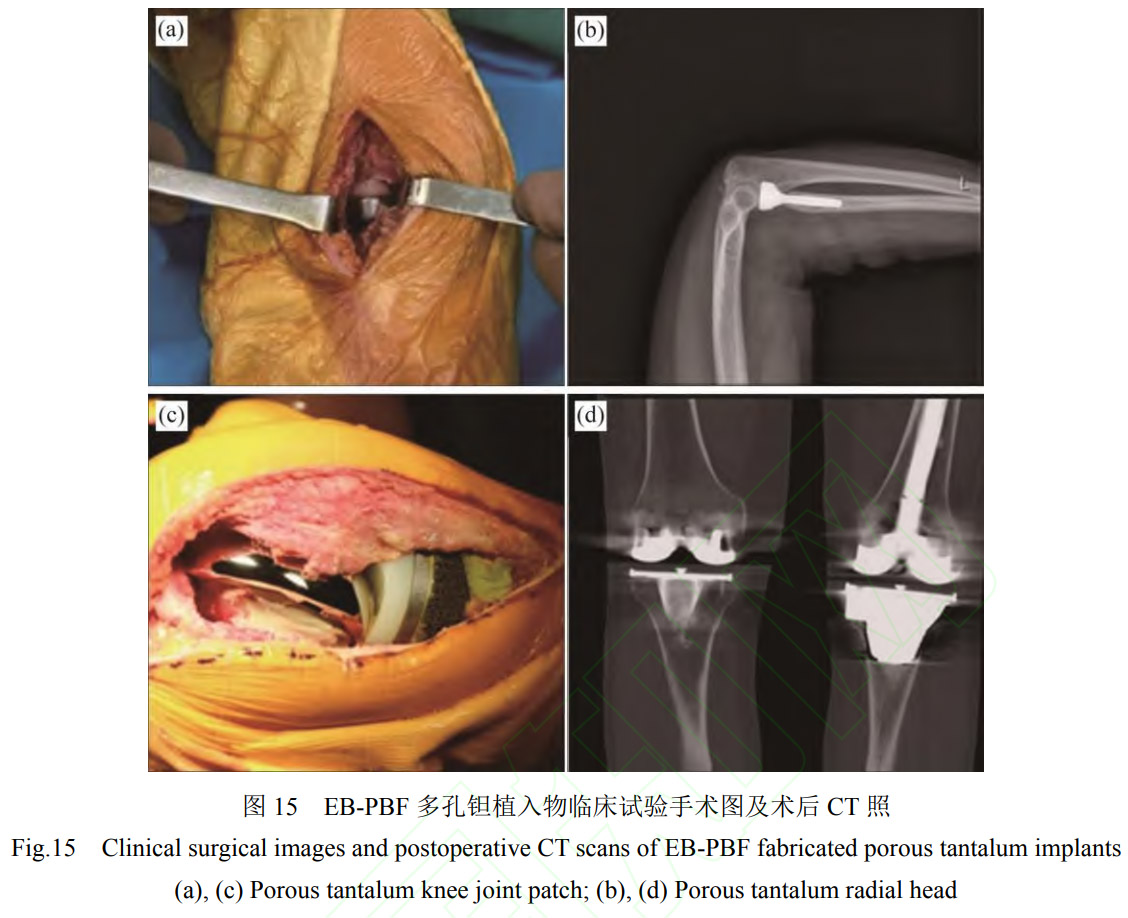

在臨床試驗方面,西安賽隆增材技術股份有限公司依托科技部國家重點研發計劃項目“個性化多孔鉭植入假體粉床電子束增材制造關鍵技術和臨床應用”項目(2016YFB101400),累計完成100余例個性化多孔鉭臨床試驗,患者年齡3~83歲,植入物包括多孔鉭髖關節補塊、膝關節補塊、橈骨假體、舟骨假體等。如ZHANG等[63]利用EB-PBF多孔鉭橈骨假體對7例橈骨頭粉碎性骨折患者進行了橈骨頭置換術,術后隨訪數據顯示,患者術后疼痛減輕,肘關節功能改善,多孔鉭假體展現出優異骨長入特性。AO等[64]觀察了6例使用EB-PBF多孔鉭膝關節補塊進行全膝關節置換術翻修患者的恢復情況,其臨床手術照片如圖15所示,在術后26.3個月后,沒有患者出現任何手術相關并發癥,植入關節內的多孔鉭假體穩定,骨缺損得到有效重建,患者膝關節功能得到明顯改善。